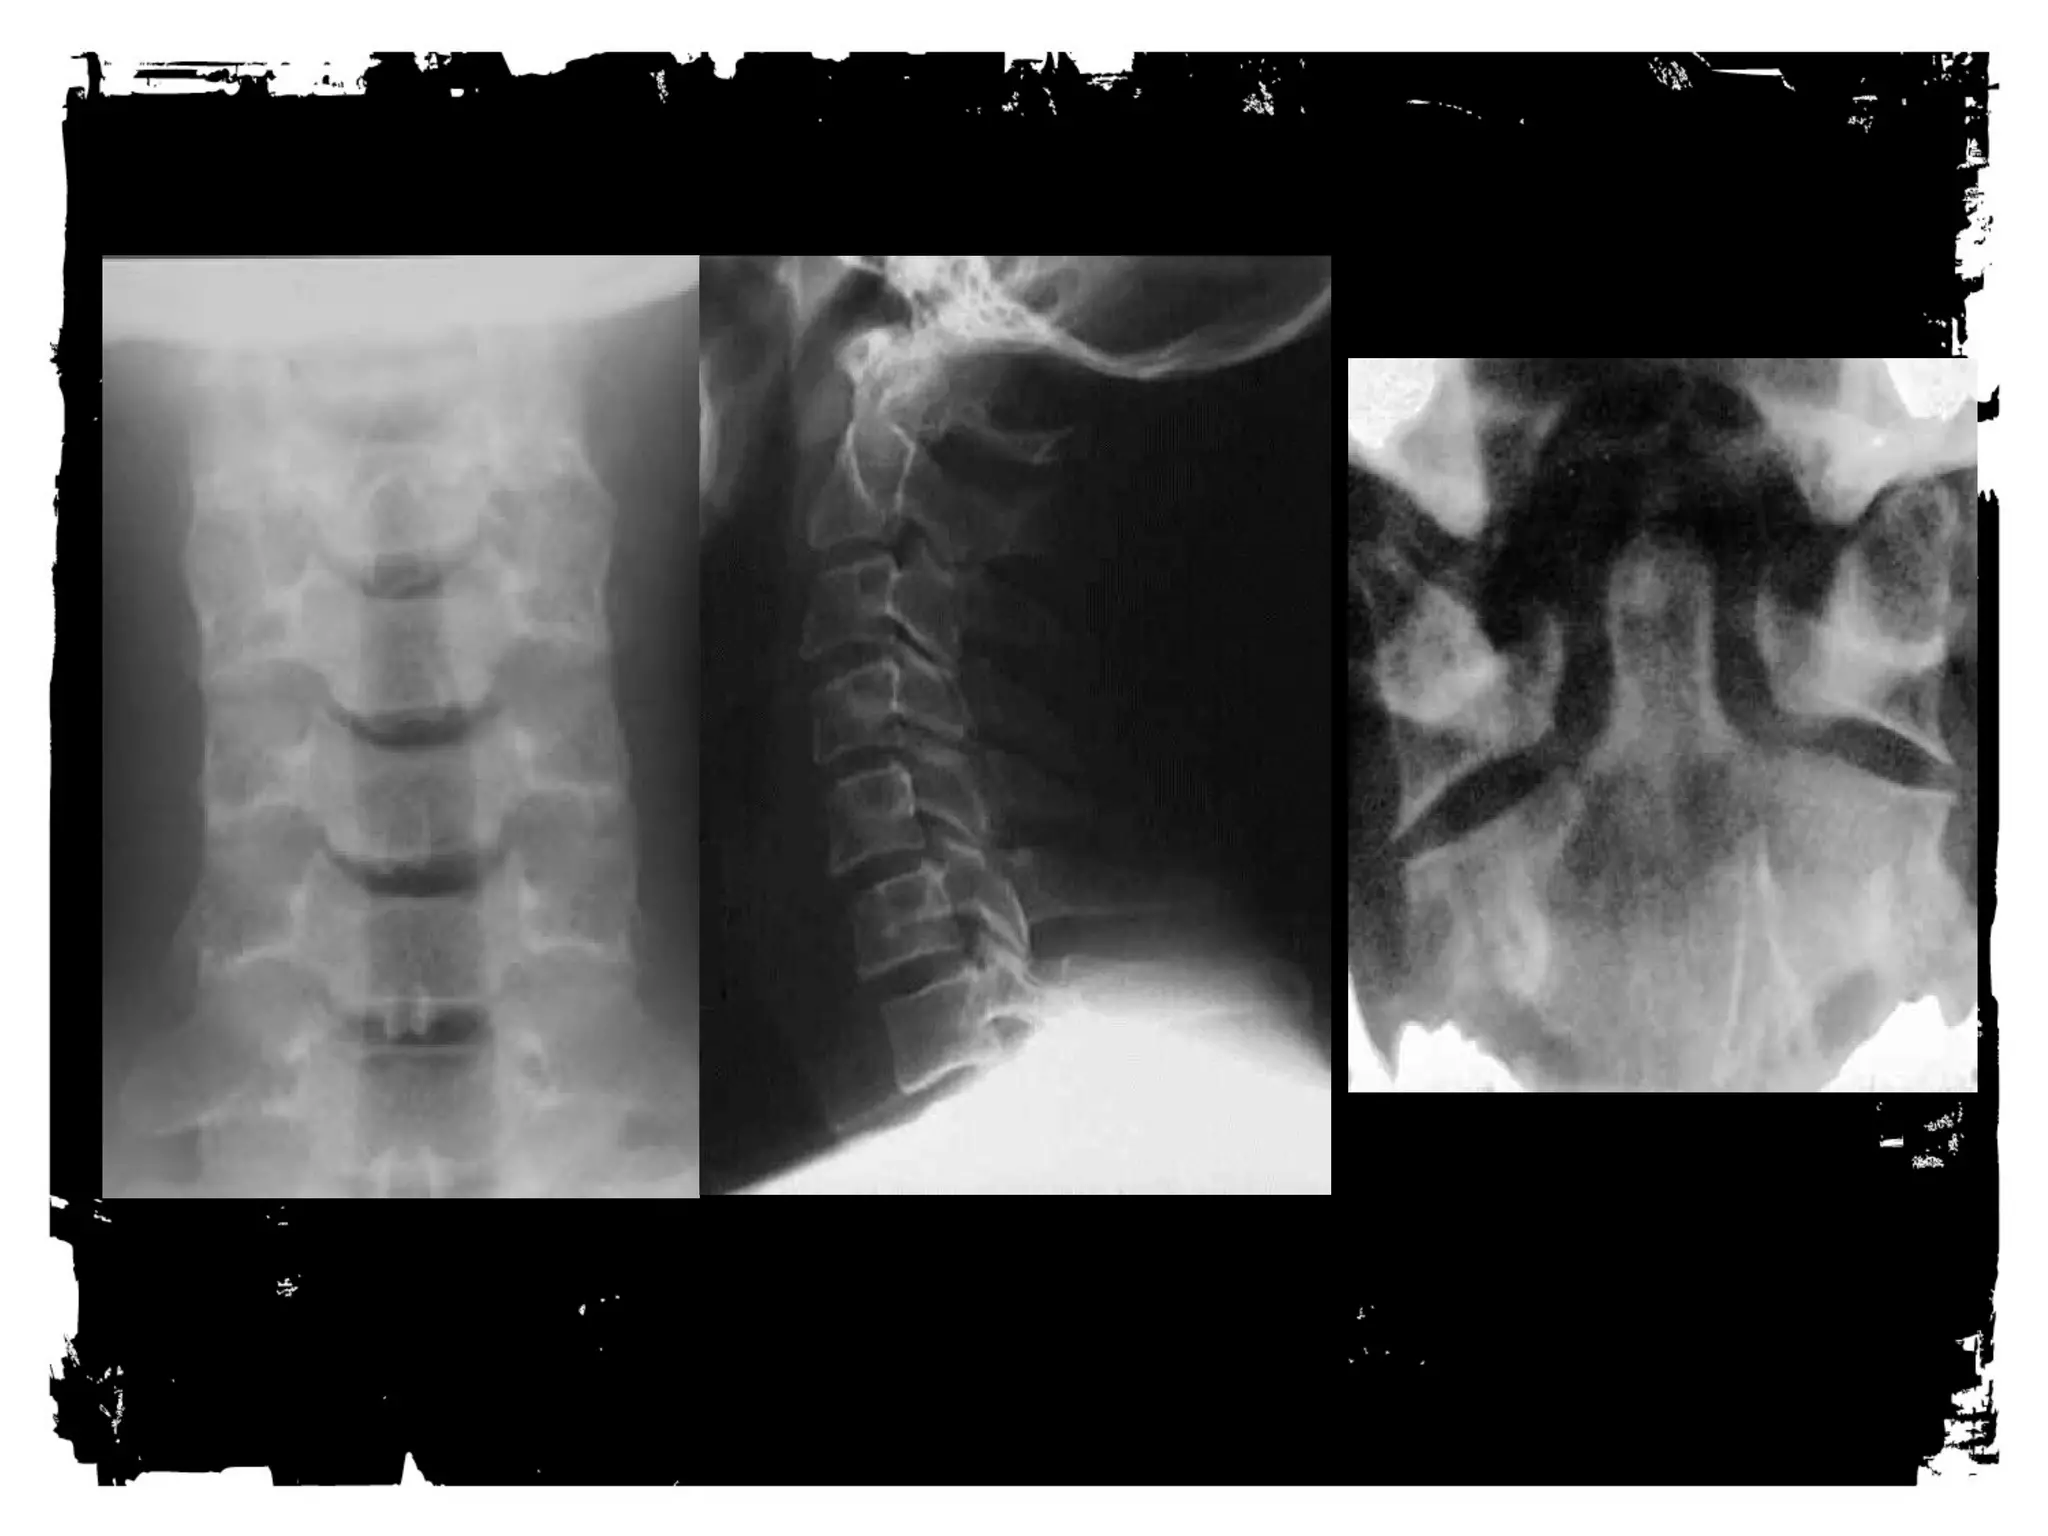

RADIOGRAPHY for primary cervical spine

screening

• Minimum standard views

– Lateral through C7

– AP

– Odontoid

• Supplementary views

• Bilateral obliques

– Swimmer’s

– Flex ion and extension

Lateral View

Base of the occiput should be visualized

Junction of C7-T1 must be visualized

A swimmer’s view taken with one arm extended over

the head can be helpful

AP view

Must include the spinous processes of all the cervical

vertebrae from C2 trough T1.

OM view

Must show relationship of the lateral masses of C1

and the odontoid process.

NNOORRMMAALL CCEERRVVIICCAALL SSPPIINNEE

1 = anterior vertebral line

2 = posterior vertebral line

3 = spinolaminar line

4 = posterior spinous line